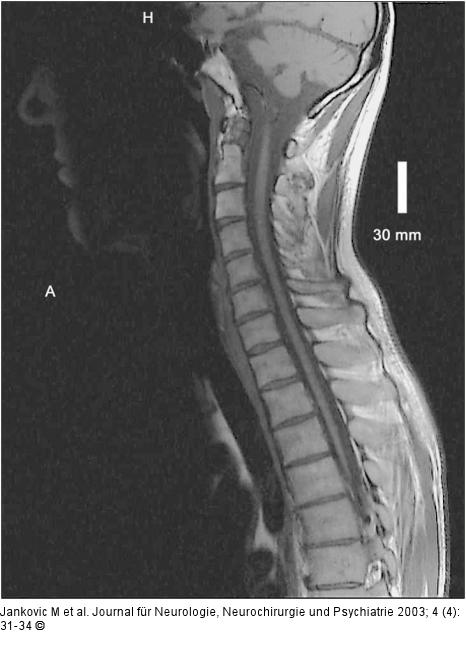

Abbildung 4: Adrenomyeloneuropathie Spinale T1-TSE sagittal: Atrophie des gesamten Myelons. |

Spinale T1-TSE sagittal: Atrophie des gesamten Myelons. |